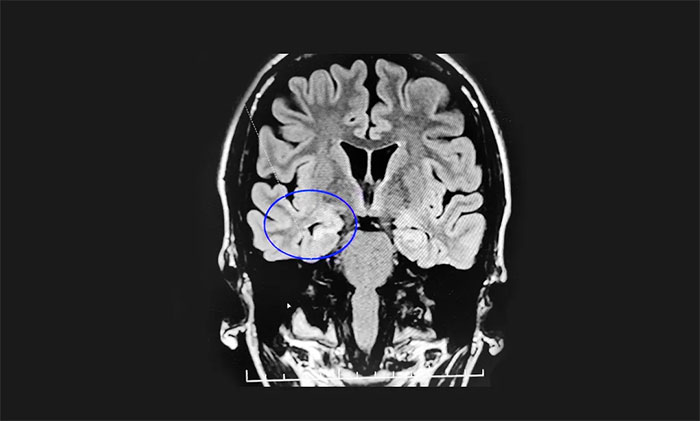

结合张女士的病史和各项检查,杨忠旭教授指出,考虑张女士为脑膜炎导致的癫痫,并且经系统内科药物治疗不佳,确诊为药物难治性癫痫。应用现代神经影像学技术和电生理监测技术,能准确定位导致癫痫发作的“责任病变”,手术指征明显,未见明显手术禁忌症。杨教授为她制定了周全的手术方案并做好充分准备。

▲ 通过系列检查,最终明确致癫灶位

8月16日,在征得家属同意后,杨忠旭教授在崔丽华主任脑电监测辅助下为患者进行了手术。切除患者张女士相关病变区域后,再次脑电监测显示脑区无异常放电,手术成功。目前,张女士正在康复中。